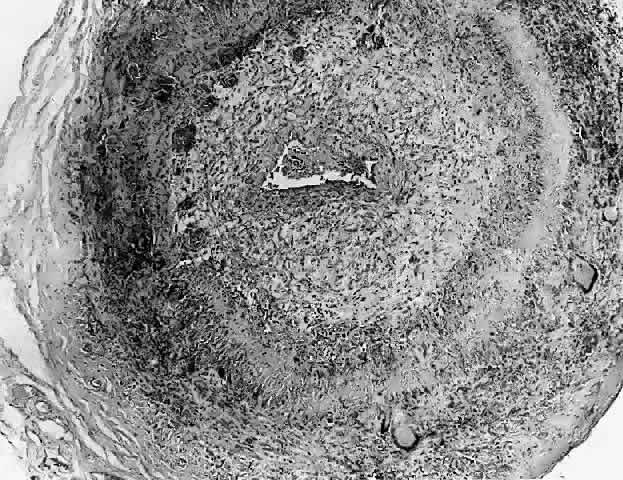

In general, idiopathic orbital inflammation is polymorphic (Figs. 5 AND 6).3,6,7,33,87,88 The cellular response seen in this disease consists of lymphocytes, plasma cells, macrophages, histiocytes, occasional neutrophils and eosinophils, epithelioid cells, and fibroblasts. These are present in varying numbers, depending on the chronicity of the inflammatory process. Intranuclear Dutcher bodies and intracytoplasmic Russell bodies may be present within many of the plasma cells since they actively participate in the inflammatory response. Children tend to have a significant number of eosinophils in their biopsy specimen. Lipogranulomatous inflammation with fat necrosis may also be present. However, the presence of noncaseating granulomas is relatively uncommon.89 This is often associated with foreign body giant cells that are responding to the release of lipid. Perivascular lymphocytic cuffing and capillary proliferation are quite common.3 Occasionally, lymphoid follicles may also be seen.

Fig. 5. Section from globe removed (in era before corticosteroid therapy) because inflammatory process had progressed inexorably to dense scar formation with resultant painful eye. Note dense ligneous tissue above globe has fused with sclera (H&E, ×4).

Fig. 6. Histopathologic sections demonstrating the various pathologic findings associated with idiopathic orbital inflammation. Most commonly these include lymphoid follicles, granulomas, collagen deposition, and a diffuse mixed inflammatory cell infiltrate. The normal tissue architecture is frequently disrupted by these changes. A. Many lymphoid follicles are scattered throughout orbital tissue (H&E, × 63). B. Cells of follicular center are lighter and larger than mantle of mature lymphocytes that surround the germinal zone (H&E, ×160). C. Lacrimal gland elements have undergone atrophy in advanced example of idiopathic dacryoadenitis. Fibrosis and lymphocytes have replaced a considerable amount of gland parenchyma (H&E, ×94). D. Myositis in which lymphocytes are loosely aggregated below center and infiltrate between extraocular muscle fibers (H&E, ×160). E. Cuffing of small vessels by mature lymphocytes. Note loose edematous interstitium between disrupted muscle fibers (H&E, ×240). F. Progressive fibrosis of retrobulbar fat (H&E, ×25).